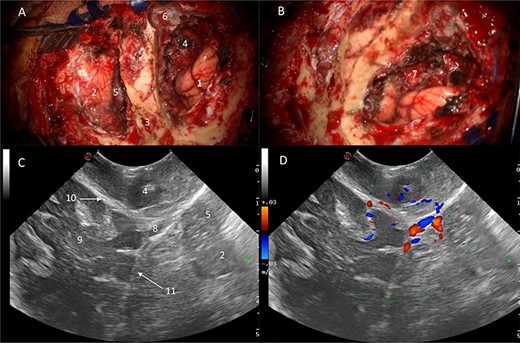

Power and colour Doppler were used throughout to obtain real-time information about the location and function of dural venous sinuses. Blood flow was preserved in the sinuses and, as we debulked the tumour, we were able to demonstrate bi-directional flow within the sinuses (Fig. 3). This suggested resolution of venous obstruction and indicated the dural venous sinuses had regained their functionality. Medially tumour was found invading the torcula and right transverse sinus, and a decision was made to leave the residual tumour and to preserve the sinuses (Fig. 4). We achieved a Simpson Grade 4 resection without any intraoperative complications.

Correlation of US appearance and gross anatomy; (A and B) intraoperative picture of the surgical field at the end of resection; (C and D) final US assessment—B-mode (C) and duplex (D); 1, ipsilateral occipital lobe; 2, ipsilateral cerebellar hemisphere; 3, strip of bone on top of the transverse sinus; 4, supratentorial resection cavity; 5, infratentorial resection cavity; 6, torcular; 7, supra-infratentorial communication of the tumour via the tentorium; 8, straight sinus; 9, contralateral occipital lobe; 10, falx cerebri; 11, tentorium.